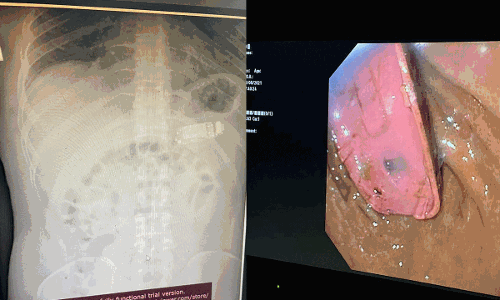

ശസ്ത്രക്രിയ നടത്തിയ ഡോക്ടർ സ്കെൻഡർ ടെലാക്കു ഫോട്ടോയടക്കം ഫേസ്ബുക്കിൽ പോസ്റ്റിട്ടതോടെയാണ് വിവരം ലോകമറിഞ്ഞത്